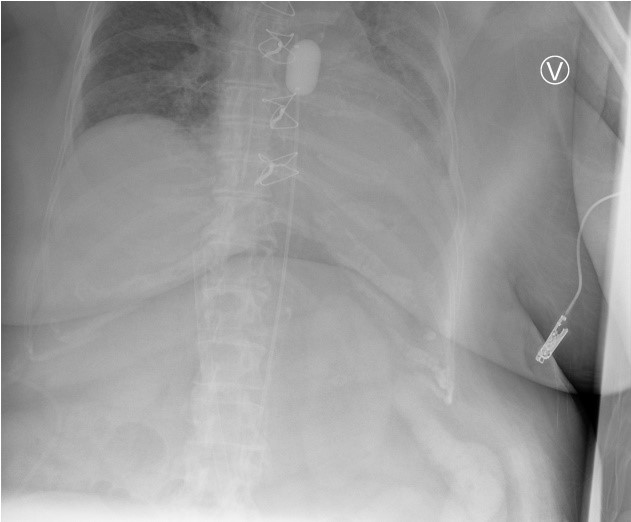

We report a case involving a cDCD donor with chronic heart disease and previous cardiac bypass surgery. The patient was admitted unconscious, showed severe global hypoxic-ischemic brain injury, and was accepted as a cDCD donor. Despite adhering to the aNRP protocol, including a 5-minute no-touch period and correct aortic balloon placement verified by x-ray, the donor spontaneously regained a heart rhythm, consequently leading to the abortion of the procedure.